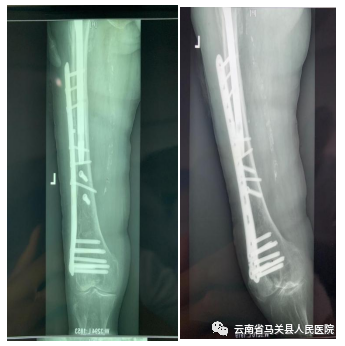

术后检查照片